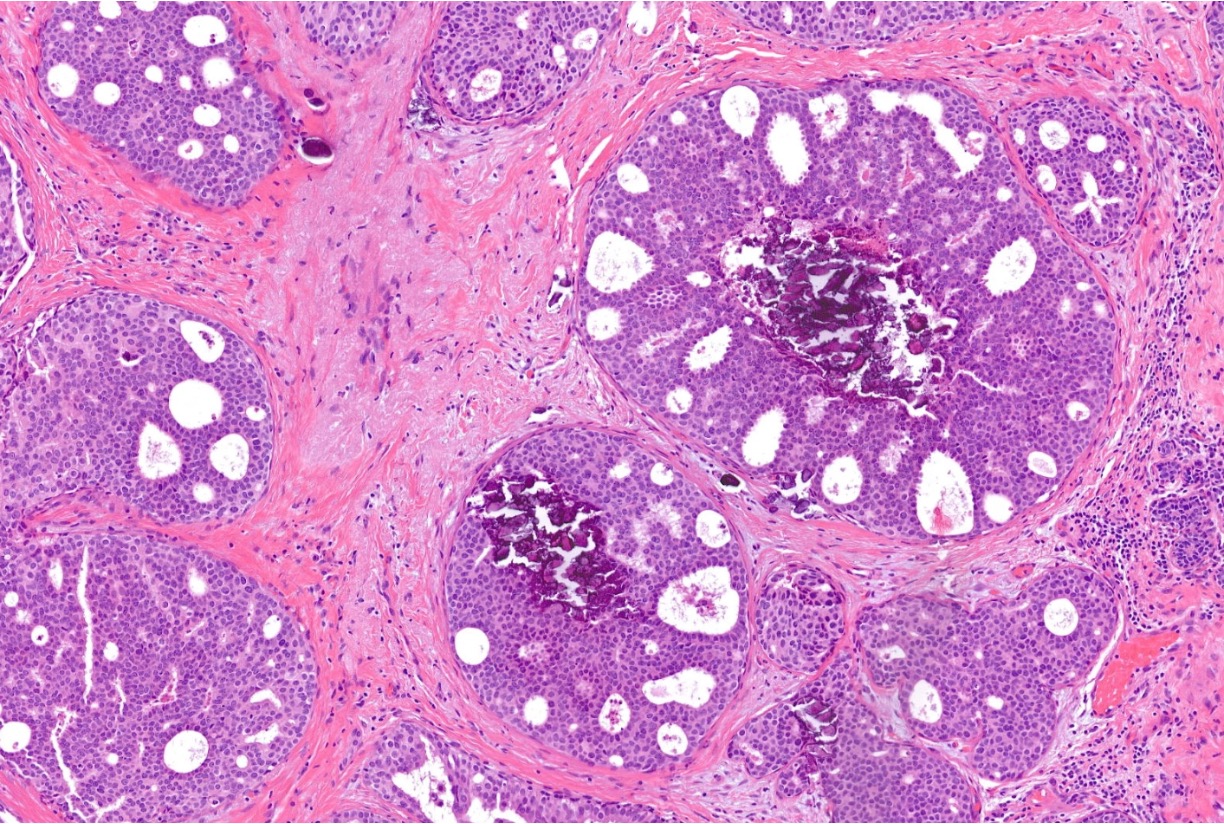

<p>Immune response to DCIS. The various types of immune cells are indicated by different colours, such as green, magenta, and red. DCIS is seen in the upper left part, indicated by the greyish cell borders.</p>